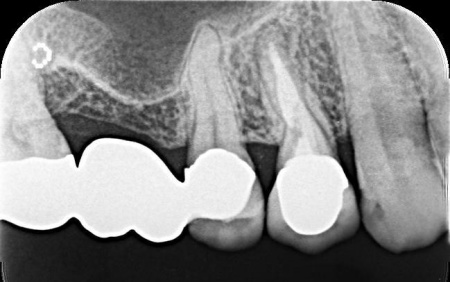

| 診断 | 拝見したところ、右上4番目の歯には白い被せ物が入っていましたが、加齢により歯ぐきが下がったことで被せ物が合わなくなり、土台が見えて黒くなっていました。

この歯は笑ったときに見えやすい部分のため審美性に影響が出ており、さらにこのまま放置すると隙間から細菌が入り込んで虫歯が再発するリスクもあります。 以上のことから、被せ物を取り外し新しい被せ物に交換する必要があると診断しました。 |

| 行ったご提案・治療内容 | 診断結果を丁寧に説明したうえで、古い被せ物を外し歯に合った新しい被せ物を作製する治療を提案し、同意いただきました。

この歯は過去の治療で被せ物を装着する際に歯の神経を取る根管治療を行っていました。 患者様は「見た目がきれいで長持ちする被せ物がいい」と希望され、被せ物の種類は自由診療のセラミックであるジルコニアクラウンを選択しています。 ジルコニアクラウンのメリット・デメリット まず古い被せ物を除去して土台の形を整え、精密な型取りを行いました。 |

治療中